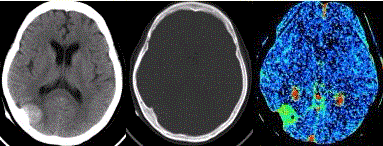

问题 患者女,60岁,头痛半月余。既往体健。腰椎穿刺检查提示脑脊液压力增高。CT及CT灌注表现如下图。 根据CT的表现,临床拟诊为

选项 A.脑血肿 B.骨瘤 C.胶质瘤 D.脑膜瘤 E.转移瘤

答案 D